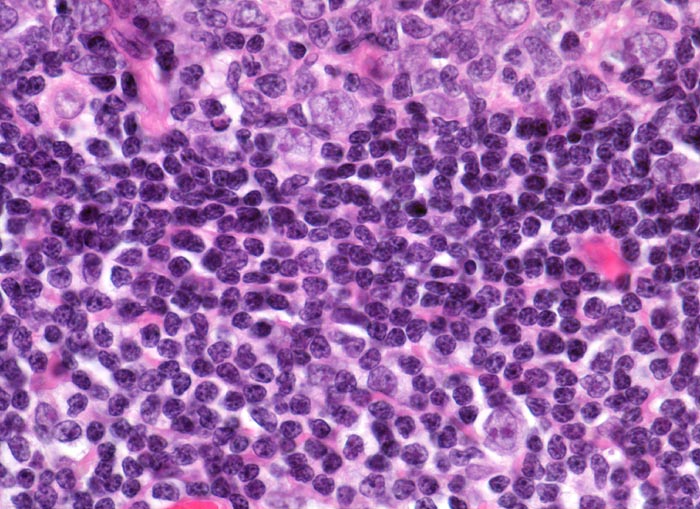

normaler Lymphknoten: Mantelzone und Marginalzone

Lymphknoten, abdominal

Oben im Bild ein Keimzentrum mit Zentrozyten, Zentroblasten und follikulär dendritischen Zellen. Angrenzend die zelldichte Mantelzone. Unten im Bild die lockerer konfigurierte Marginalzone mit eingestreuten dendritischen Zellen mit sternförmigen Zytoplasmaausläufern und Blasten mit grossen Kernen.

Perikolischer tumorfreier Lymphknoten aus dem Abflussgebiet eines wenig fortgeschrittenen Kolonkarzinoms.

630